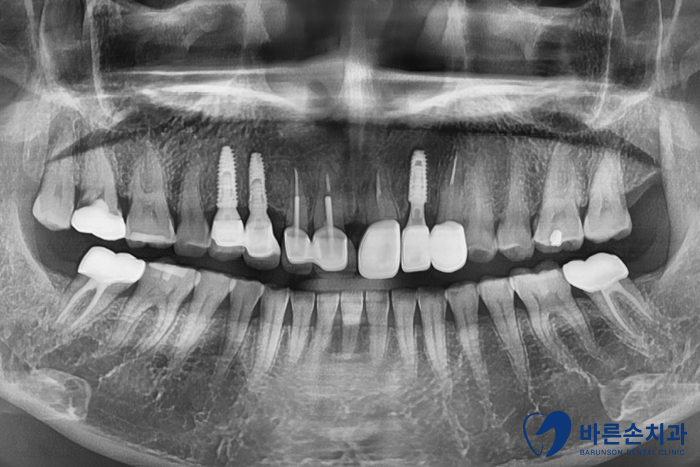

상태 체크를 위해 구내 사진과 엑스레이 촬영을 먼저 하였습니다!

치아 한 개가 상실되어 양 옆 치아를 연결해서 만든 보철물을 브릿지라고 하는데요.

브릿지가 빠져있고 남아있는 치아를 보니 연결해서 쓰던 치아 내부에 2차 충치가 생겼습니다.

이미 상실된 가운데 치아에는 임플란트,

양 쪽 2개 치아는 신경치료 한 후 다시 크라운 치료를 하기로 합니다.

치료기간 단축을 위해

가운데에는 임플란트를 바로 심었습니다!